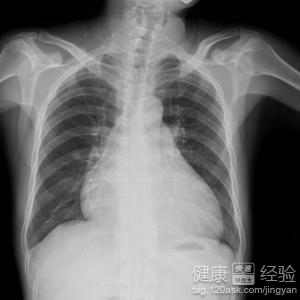

風濕性心髒病可以藥物調理嗎

爸爸的心髒功能一直都不是很好,隨著年齡的增長,工作的勞累,病情越來越嚴重了,一直都是在靠藥物治療,前一段時間病情特別不穩定,去醫院檢查,醫生說是風濕性心髒病,醫生建議最好是做心髒手術,可是爸爸不想做手術,病就一直這樣拖著,看著他被病痛折磨我的心裡也可特別不好受,想讓爸爸早些康復,不知道有沒有什麼藥物治療效果好一些?

2如果病患想要用藥物進行調理,最好的辦法就是采用中西結合的治療方式,在醫生的指導下按時服用藥物,再配合中醫的針灸,可能對緩解病痛有更好的效果,在一定程度上減輕病痛的折磨。

3如果病情一旦復發就要進行相關的手術治療,目前風濕性心髒病的手術技術已經非常成熟,成功率較高,如果病情不是特別嚴重或者沒有其他並發症,手術還是很安全的,並且可以在根本上治愈病症。